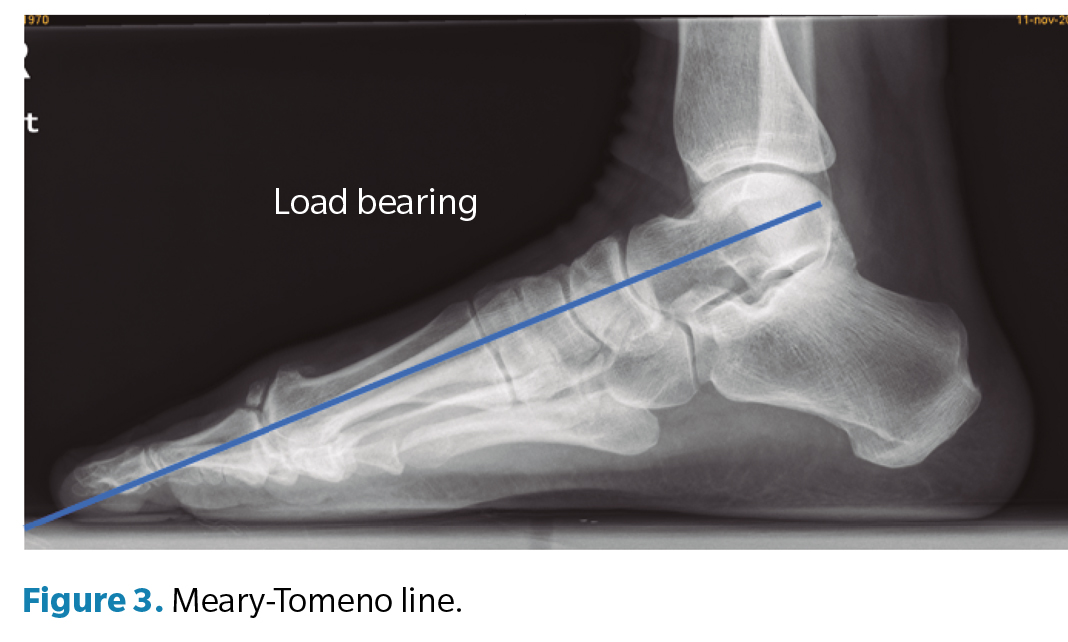

Regarding the goniometric variables in the lateral X-ray, the following angles were obtained: first metatarsal inclination angle, calcaneal inclination angle, Meary-Tomeno line, and internal Costa Bartani angle. The metatarsal inclination angle or Fick angle involves the inclination of the 5 metatarsals; however, for this study, only the inclination angle of the first metatarsal was considered (Figure 1), which was defined by the diaphyseal axis of the first metatarsal with the horizontal plane of the ground support11. The calcaneal inclination angle (Figure 2) is defined by the axis of the calcaneus, a line connecting the calcaneal tuberosity to the plantar margin of the anterior extension of the calcaneus near the calcaneocuboid joint, and the support plane (line formed by the proximal plantar tuberosity of the calcaneus and the head of the 5th metatarsal). A value of 20° is considered normal(12). The Meary-Tomeno line (Figure 3) is defined as the line passing through the axis of the talus (bisector of the angle formed by the tangent to the superior and inferior borders of the talus) and the axis of the diaphysis of the first metatarsal13). The internal Costa Bartani angle (Figure 4) is defined as the union of 3 points: the lowest point of the medial sesamoid, the lowest point of the posterior tuberosity of the calcaneus, and the lowest point of the talonavicular joint(14)..

These angles were chosen because they best represent the alignment of the internal longitudinal arch, in which the decrease or inclination towards the plantar side is associated with flattening of the arch(15).